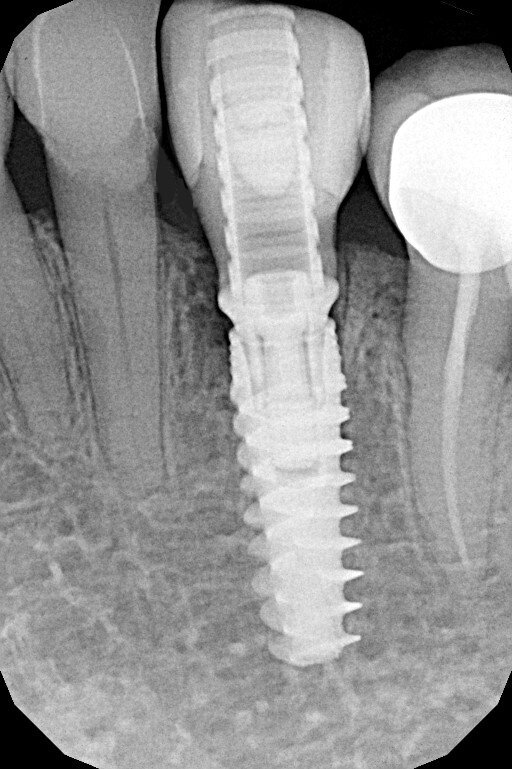

L’esame di primo livello (radiografia endorale) mostra la presenza di un minus dei tessuti calcificati a carico della radice. Si impone per ovvie ragioni un approfondimento volumetrico 3D: soltanto una CBCT ci consentirà di localizzare correttamente la lesione e valutarne la posizione, l’estensione e l’eventuale recuperabilità dell’elemento dentario. Il taglio trasversale della radiografia 3D mostra un riassorbimento radicolare esterno che riguarda la porzione linguale dell’elemento dentario (Figg. 1-4). Il riassorbimento presenta una posizione particolarmente sfavorevole, in quanto si estende già al di sotto del margine osseo crestale su un elemento dentario peraltro già trattato da un punto di vista protesico (Figg. 2, 3). Le opzioni terapeutiche proposte alla paziente sono sostanzialmente due: trattamento endodontico e rifacimento del restauro protesico, previo accesso chirurgico sul lato linguale con allungamento di corona clinica, oppure impianto post-estrattivo con tecnica Socket-Shield. La paziente sceglie questa seconda opzione e firma regolare consenso informato.

Fig. 4_Rx 2d e 3D, con evidenziazione del riassorbimento radicolare, che riguarda l’aspetto linguale e si approfondisce al di sotto del margine della corticale ossea; pianificazione implantare su apposito software di progettazione.

Fig. 13_Rx di fine intervento.

Fig. 20_Rx finale alla consegna della corona definitiva.